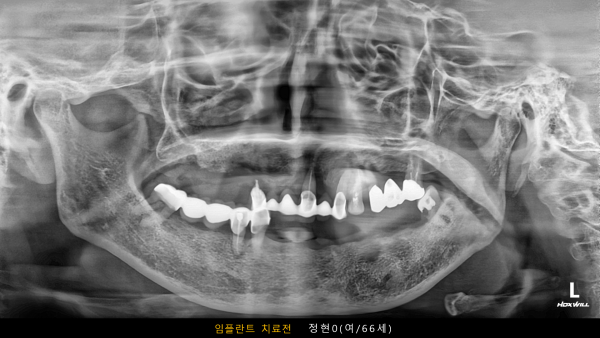

고난도 센터 | 여) 66세